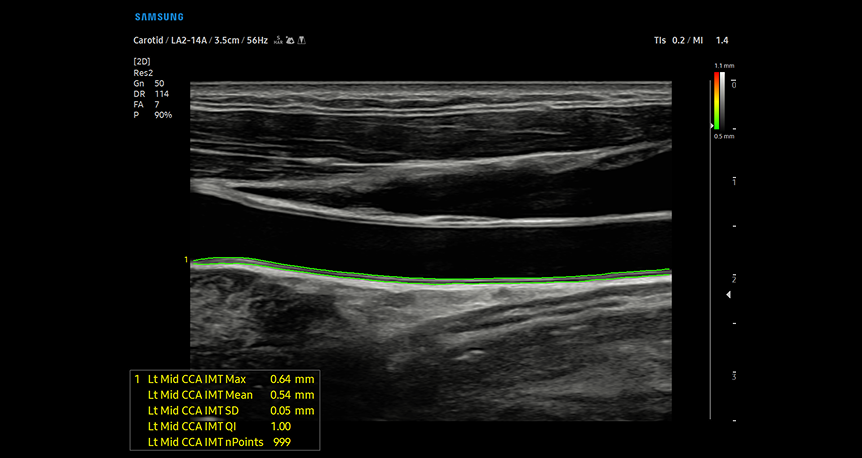

AutoIMT+

AutoIMT screening technology providing automated measurement of carotid artery intima-media thickness with precise quantification to assess cardiovascular disease risk factors

AutoIMT+ è uno strumento di screening per analizzare il rischio potenziale di malattie cardiovascolari del paziente. Consente di misurare facilmente lo spessore dell'intima della parete anteriore e posteriore della carotide comune con un semplice clic.